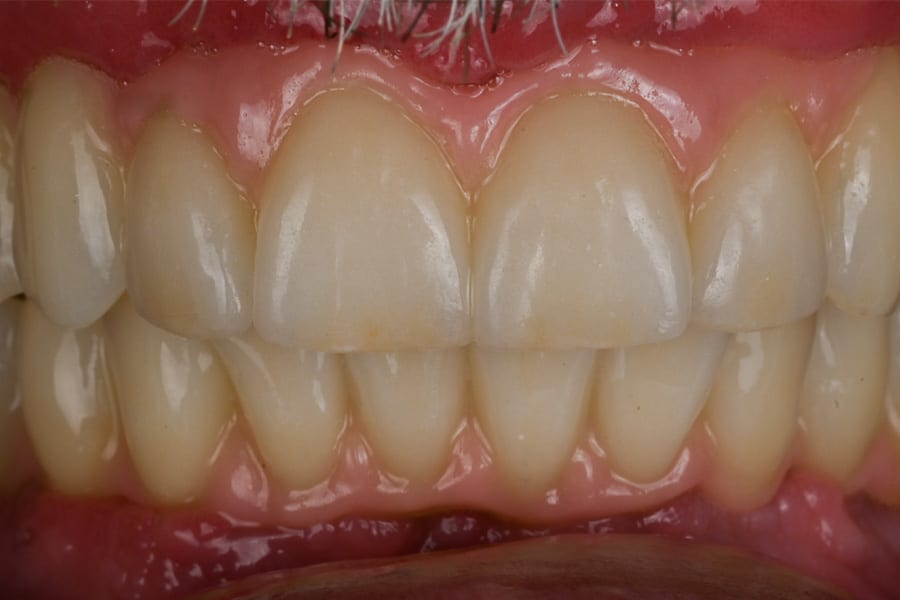

Occlusion was once again validated using jaw-motion tracking, confirming harmony with functional dynamics (Figure 28). The definitive prostheses were delivered as screw-retained restorations, achieving esthetic integration, functional stability, and patient satisfaction (Figure 29 and Figure 30).

Outcome

At delivery, the patient exhibited a harmonious smile, improved function, and increased confidence (Figure 31). Postoperative radiographs confirmed correct implant positioning (Figure 32). At the 6-month follow-up, peri-implant tissues remained stable, and no mechanical complications were reported.